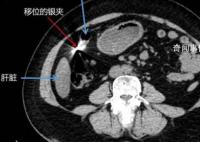

女子车祸后就医体内发现金属异物

11月3日,东莞市的街头,李女士不慎与一辆小车相撞,随后被120急救车紧急送往医院。在医院进行的检查中,医生却发现了令人震惊的情况,李女